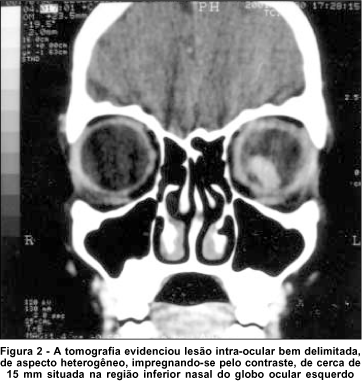

Avaliação clínica e laboratorial detalhada não mostrou alterações, além de sorologia positiva (Ig M = 1/40) para toxocaríase. A tomografia computadorizada de crânio e órbitas evidenciou lesão intra-ocular bem delimitada, de aspecto heterogêneo, impregnando-se pelo contraste, de cerca de 15 mm situada na região inferior nasal do globo ocular esquerdo (Figura 2). A ultra-sonografia mostrou uma massa intra-ocular sólida na cavidade vítrea com interior de média refletividade e picos de alta refletividade sugerindo pontos de calcificação (Figura 3). Foram feitas as hipóteses diagnósticas de retinoblastoma, membrana ciclítica por toxocaríase e doença de Coats, além de persistência de vítreo primário hiperplásico e meduloepitelioma intra-ocular.